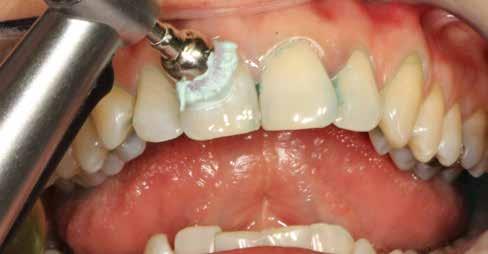

sok korrigálása, valamint az impaktálódott fog előtöréséhez szükséges hely megteremtését követően, egy merev acél ív segítségével stabilizáltuk a fogakat. Ezt követően elvégeztük a jobb felső nagymetszőfog sebészi feltárását. A fog koronáját csupán lágyrész borította, ezért nem volt szükség a csontállomány elvételére. A felszabadítás során egy 975

nm-es hullámhosszon pulzáló üzemmódban alkalmazott lézert használtunk (LaserHF standard, Hager & Werken). A teljesítménye 3 W, az aktív ciklus-idő 50%-os, a vezetőszál átmérője pedig 0,4 mm volt (2. ábra). A lézert 150 másodpercen keresztül alkalmaztuk. A fogat borító lágyrészek eltávolítását követően egy láncos brekettet rögzítettünk a metszőfog bukkális felszínére. A műtétet követően nem tapasztaltunk vérzést, nem alakult ki oedema, valamint a páciens sem számolt be fájdalom vagy bármely egyéb kellemetlenség fennállásáról. A felszabadítást követően a páciens minden hónapban háromszor jelent meg a felszabadított területre ránövő lágyrészek és az íny lézeres eltávolítása céljából. A beavatkozások során ugyanazt a lézer készüléket használtuk, mint amivel a felszabadítást végeztük. Közvetlenül a felszabadítást követően megkezdtük a fog finom extrudálását a láncos breketthez kötött füzérgumi segítségével.